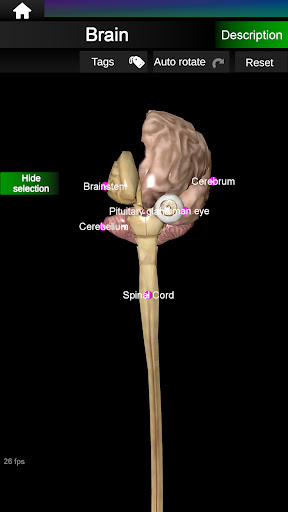

* Brain, which includes the brain, cerebellum, and brain stem.

Shows a 3D anatomical model of the main organs of the human body and a description of each one.

* Easy to access and navigate (zoom, 3D rotation).

* Hide or show information.

* Descriptions of each organ.